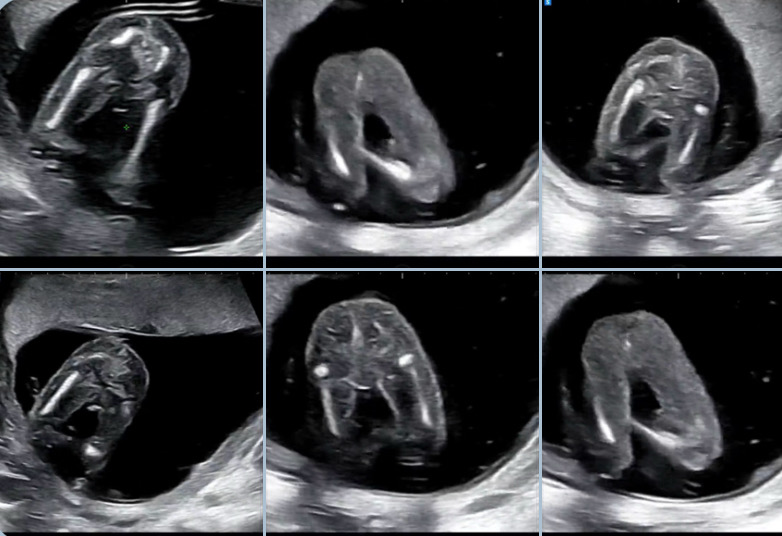

안녕하세요~ 오늘 처음 성별 확인라는 날이어서 설레는 마음으로 병원에 다녀왔어요 사진은 15주차 4일이에요! 선생님도 애매하다고 확정은 안해주셔서 다음에 올때까지 더 지켜보자고 하시네요!? 일단 아들같기도하고 딸이 부어있는것 같다고도 하셨어요 “일단 아들로하죠!” 라고 끝났어요 엄마들 생각도 궁금해요~ 자유롭게 의견 부탁드려요~